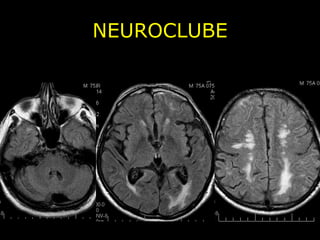

NEUROCLUBE Angiopatia Amilóide Cerebral - Depósito de proteína b-amilóide cortical, subcortical e leptomeninge; - Hemorragia cerebral em normotenso; - Assintomático e sintomático;

NEUROCLUBE CASO 2